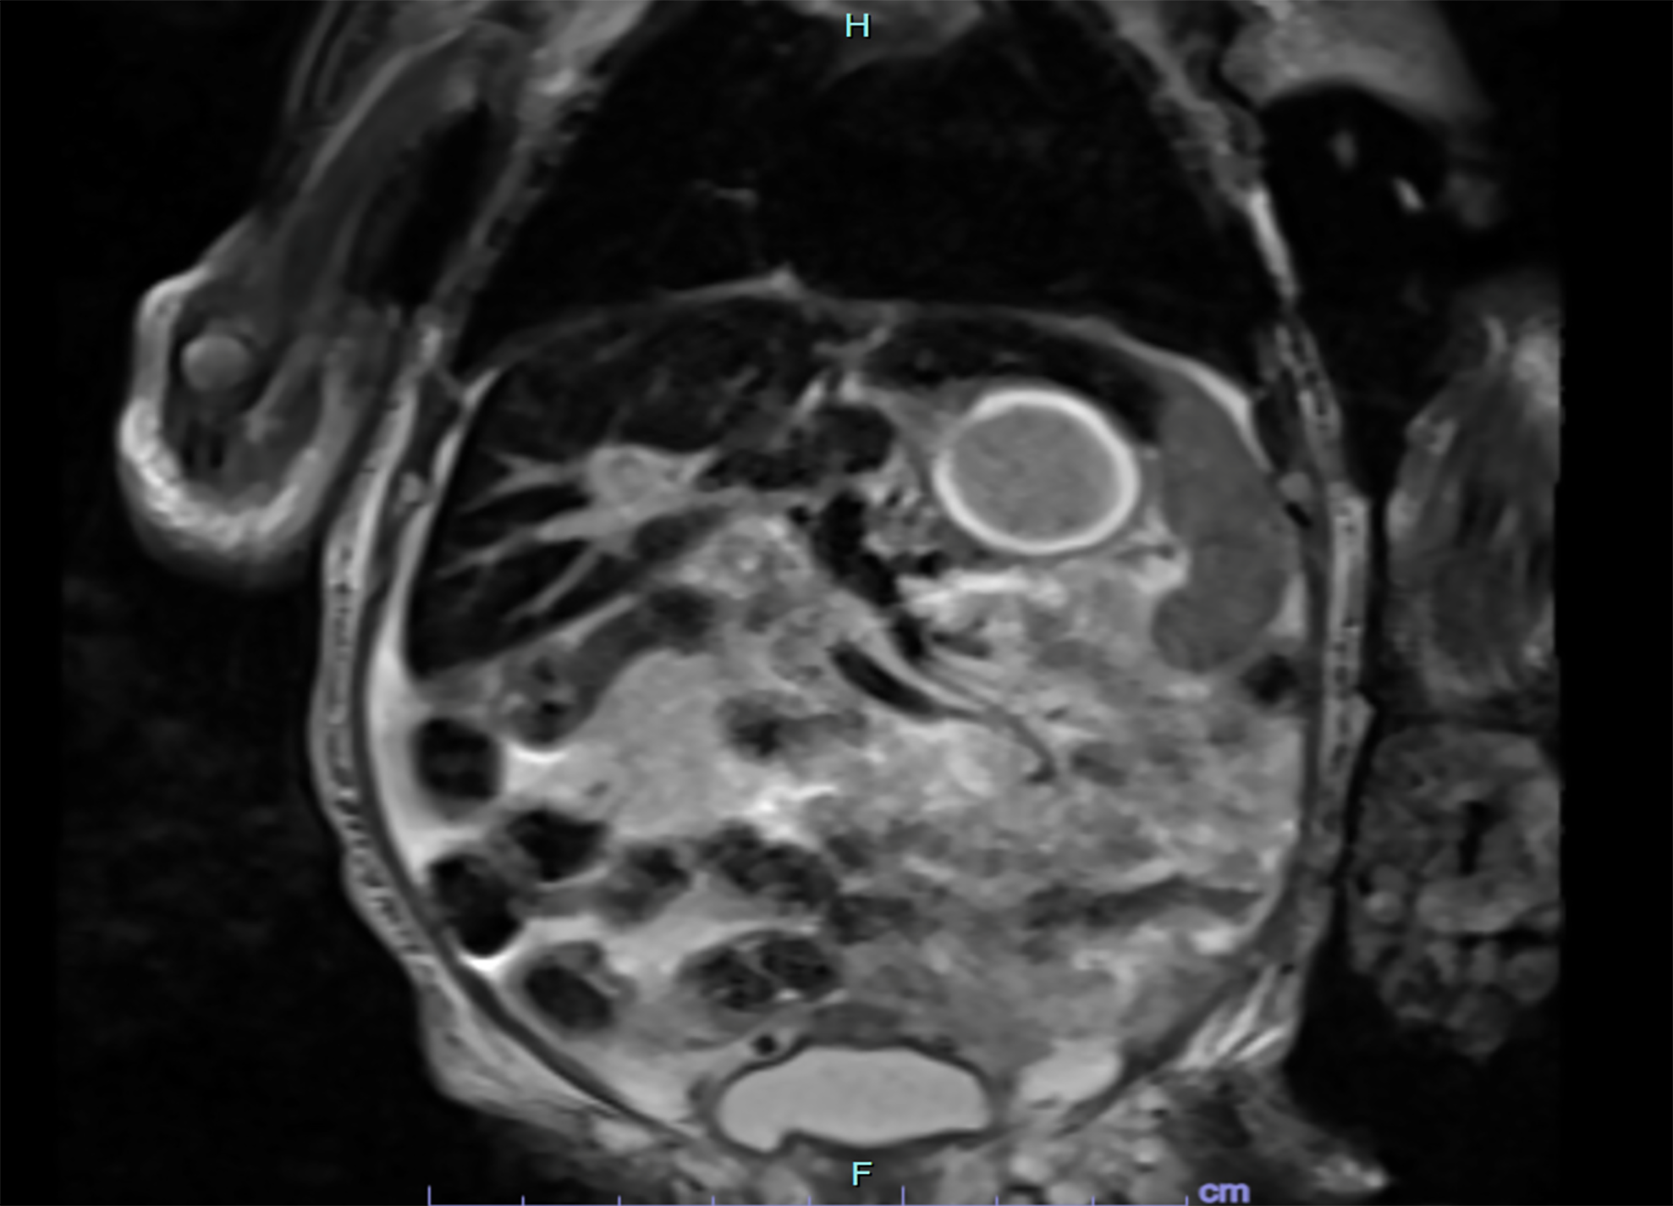

Figure 1 T2 signal loss in liver (case 4).